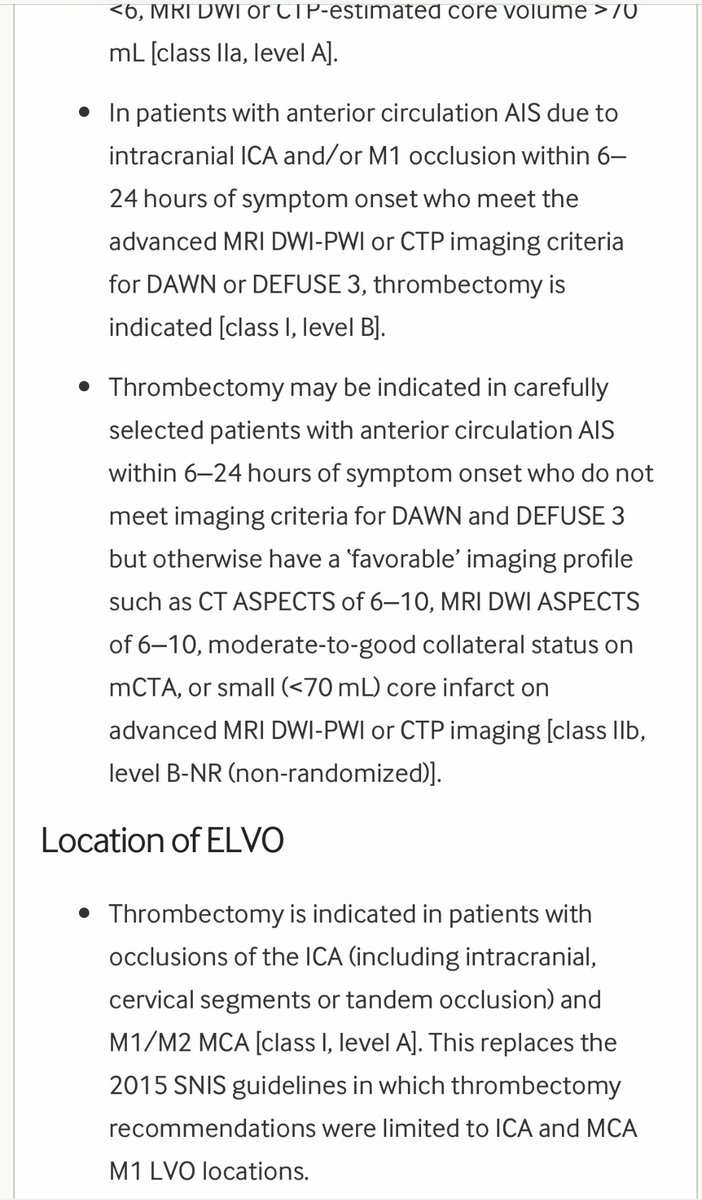

للاطباء المهتمين في علاج السكتات الدماغيه الحاده

Latest 2019 guidelines for acute stroke

ahajournals.org

Other recommendations attached 👇👇

Latest 2019 guidelines for acute stroke

ahajournals.org

Other recommendations attached 👇👇